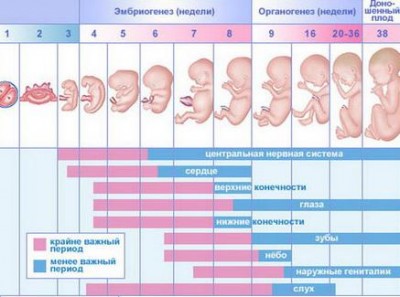

Tehát, az első héten a csírasejt tárcsa alakú, és osztódni kezd, de a végén azt beültetik a méhbe. A negyedik héten alakult a fej, a szív, a végtagok, a vérkeringés jön létre. Bár az embrió még apró, fejlődik az agy, a gerincvelő és a fej fény. Aztán a hatodik héten már vannak jelei a szem, orr, fül. Embrionális periódus véget ér 11 hét. Úgy kezdődik, a következő lépés a fejlődés.

Sok tudós javasolom, a humán embrió egy 12 hetes, ahogy alakult a kezdetektől szinte minden szerv és az is meghatározza annak a szex.

Tanulmányozásával, ami egy gyermek a méhben hetekig a fotó, a brit tudósok megállapították, hogy tudta mozgatni már 12 hetes. Egyszerűbben ez olyan kicsi, hogy az anya nem érzi ezt a mozgást. Csakúgy, mint az elején a második trimeszterben a magzat képes arra, szopás mozgásokat. Úgy néz ki, mint egy férfi: szemek várjuk, csontváz kosteneet megjelenik a zsír a bőr alatt. A gyermek agya fokozatosan alakul ki, alkotó apró nogotochki kialakítva a hangszálak. Van még egy arckifejezés! Vesék már működik.

A 17-20 hetes terhesség, magzati mérete koronát far - 13-15 cm, és a súlya több mint 200 gramm. De anya már úgy érzi, a különböző mozgások gyerek. És hallja a hangokat a test az anya képes felismerni a hangját, és a hangja a partner, a beszélgetést vele. Persze, a hang tompa, mint a füle borítja vastag viaszos bevonattal, amely megvédi a bőrt a folyadék. Midway Travel! A következő hetekben a 2. trimeszterben, a baba ízlelőbimbók vannak kialakítva a fej haj nő. Rendszeresen alszik és felébred.

Egészségügyi szakemberek és a szülők mindig keresnek néhány fontos mérföldkövek a magzati fejlődését a baba. Az első észrevehető, és fontos jele tartják a szívverés a növekvő gyermek. Bár a szív alakul már az első trimeszterben, de ezt a mágikus pillanatot, amikor hallja a szívverését Csád először szerint az American Medical Association, jön a 15-18 héten. Újabb mérföldkő tekinthető az időszak, amikor a gyermek neme lehet tanulni. Genitalia fejlődnek a 11 hét, de lehet látni valamit az ultrahangon, a legvalószínűbb, jön legkorábban 20 hetes terhesség. Sok gyerek egészen a születés ápolja a titkát. De a szülők még mindig várnak, hogy néz ki és a szeretet, nem számít, mit.